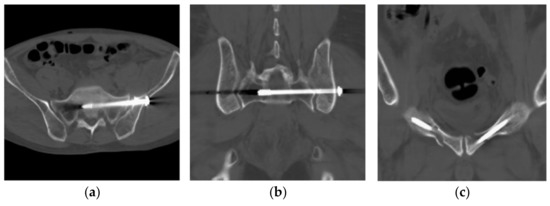

2. Case Report